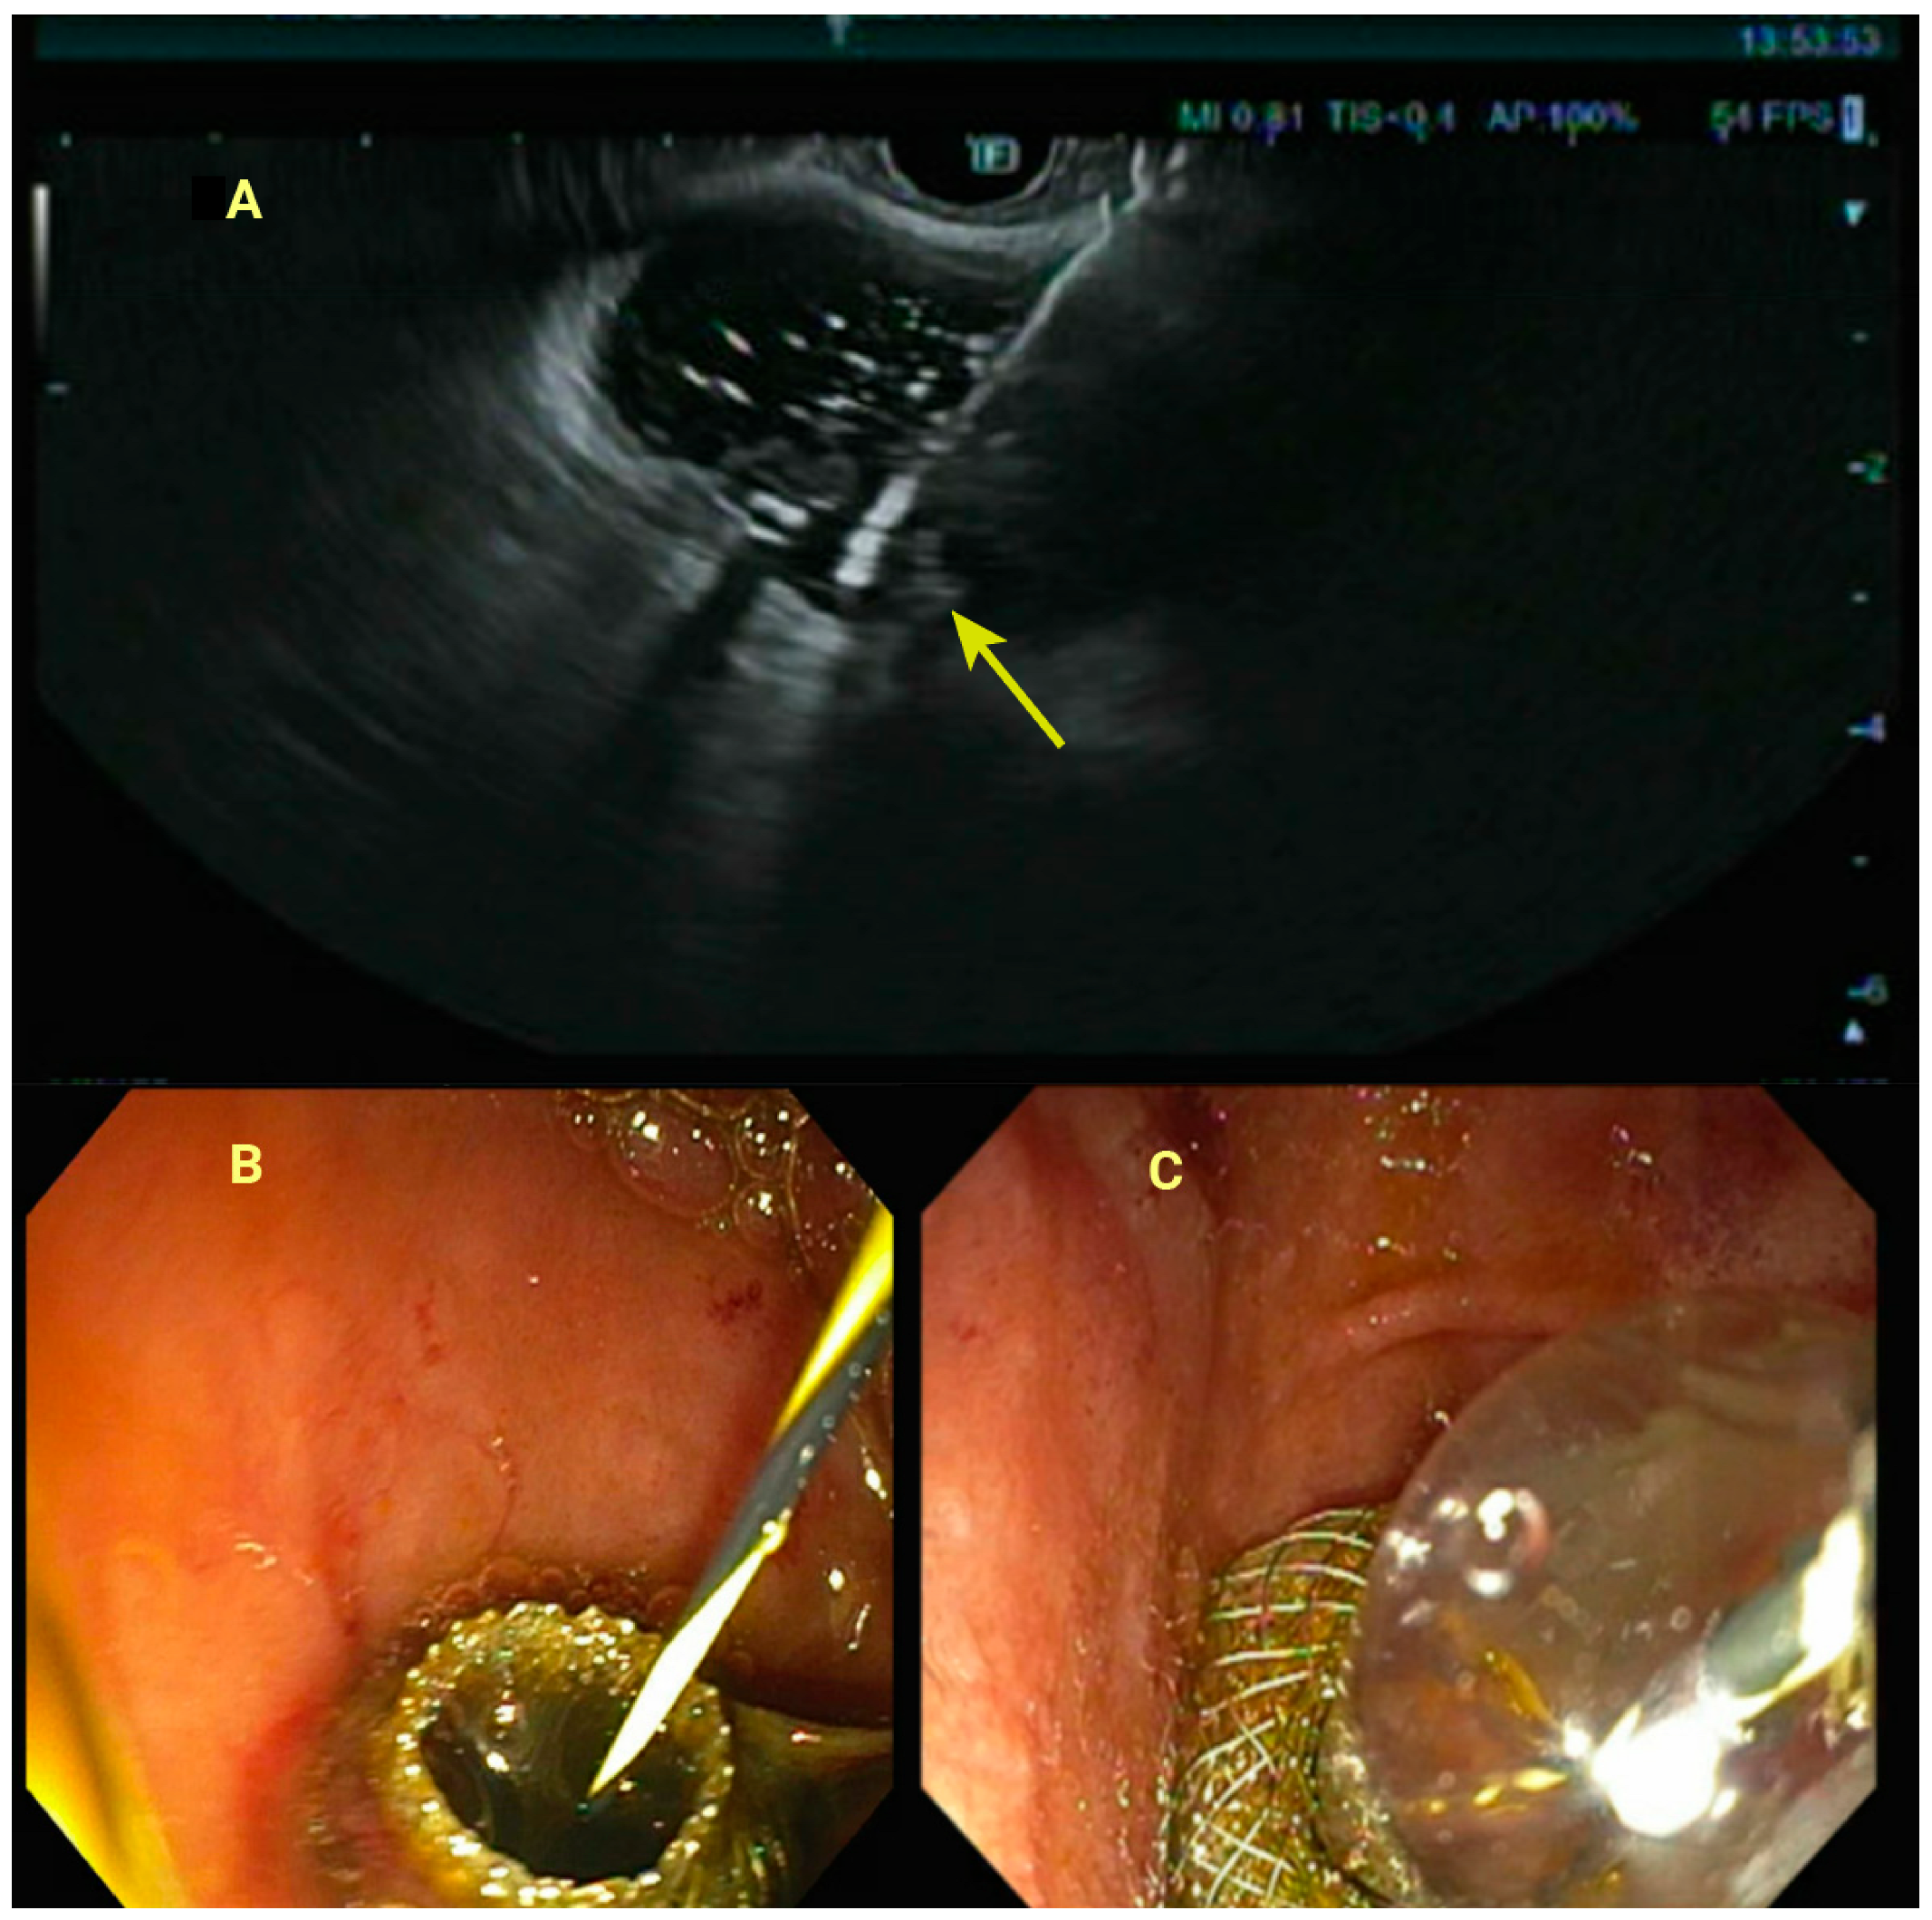

3.4. Endoscopic Ultrasound-Guided Gallbladder Drainage (EUS-GBD)